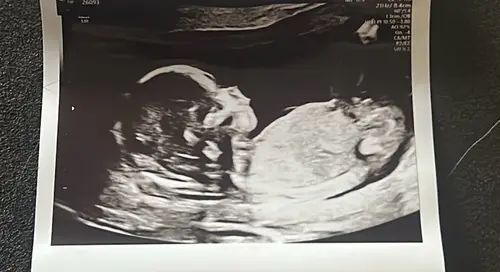

Kan iemand mij helpen bij deze? 14+2 volgende week Officele geslachtsecho maar toch erg nieuwsgierig wat jullie denken hihi:)